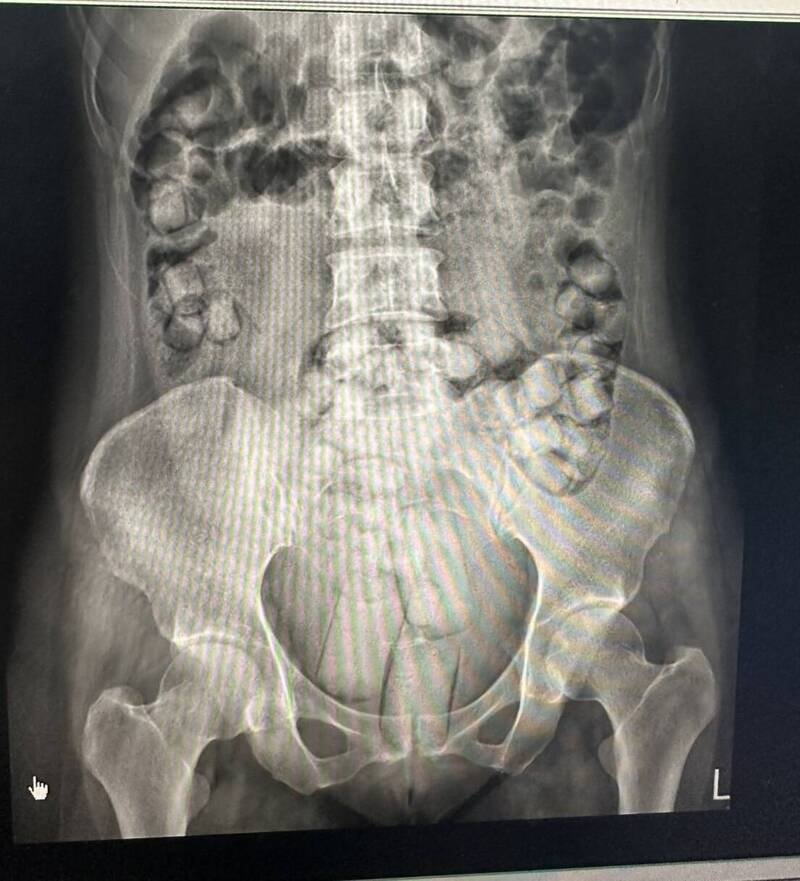

一颗都不能少!海巡署侦防分署台中查缉队于8月初接获人体运毒情资,9月7日在高雄小港机场查获2名泰国籍女子,以人体夹带及吞食方式走私海洛因,据了解,海洛因纯度高达79%,万一保险套不慎破裂,毒品被人体吸收,会当场毙命,两人在警方戒护下,在医院耗时10多个小时,顺利排出105颗大大小小的毒品,众人松了一口气。

海巡署今日指出,两名女子在曼谷透过吞食跟塞肛门方式藏毒,分别吞食或塞入54颗2百多克与61颗3百多克毒品,她们要清楚记得数字,抵台后要尽快排出毒品,一颗都不能少。

两人事迹败露,在小港医院透过灌肠跟吞泻药方式,前后排泄10多次,数量一度短少,大家都很紧张,当排泄出最后一颗时,共耗时10多小时,顺利取出所有毒品,众人松了一口气,但两女面对重刑审判,恐在台服刑10年以上才能返乡。

泰籍女子在医院耗费10多小时,才顺利排泄出毒品。(海巡署提供)